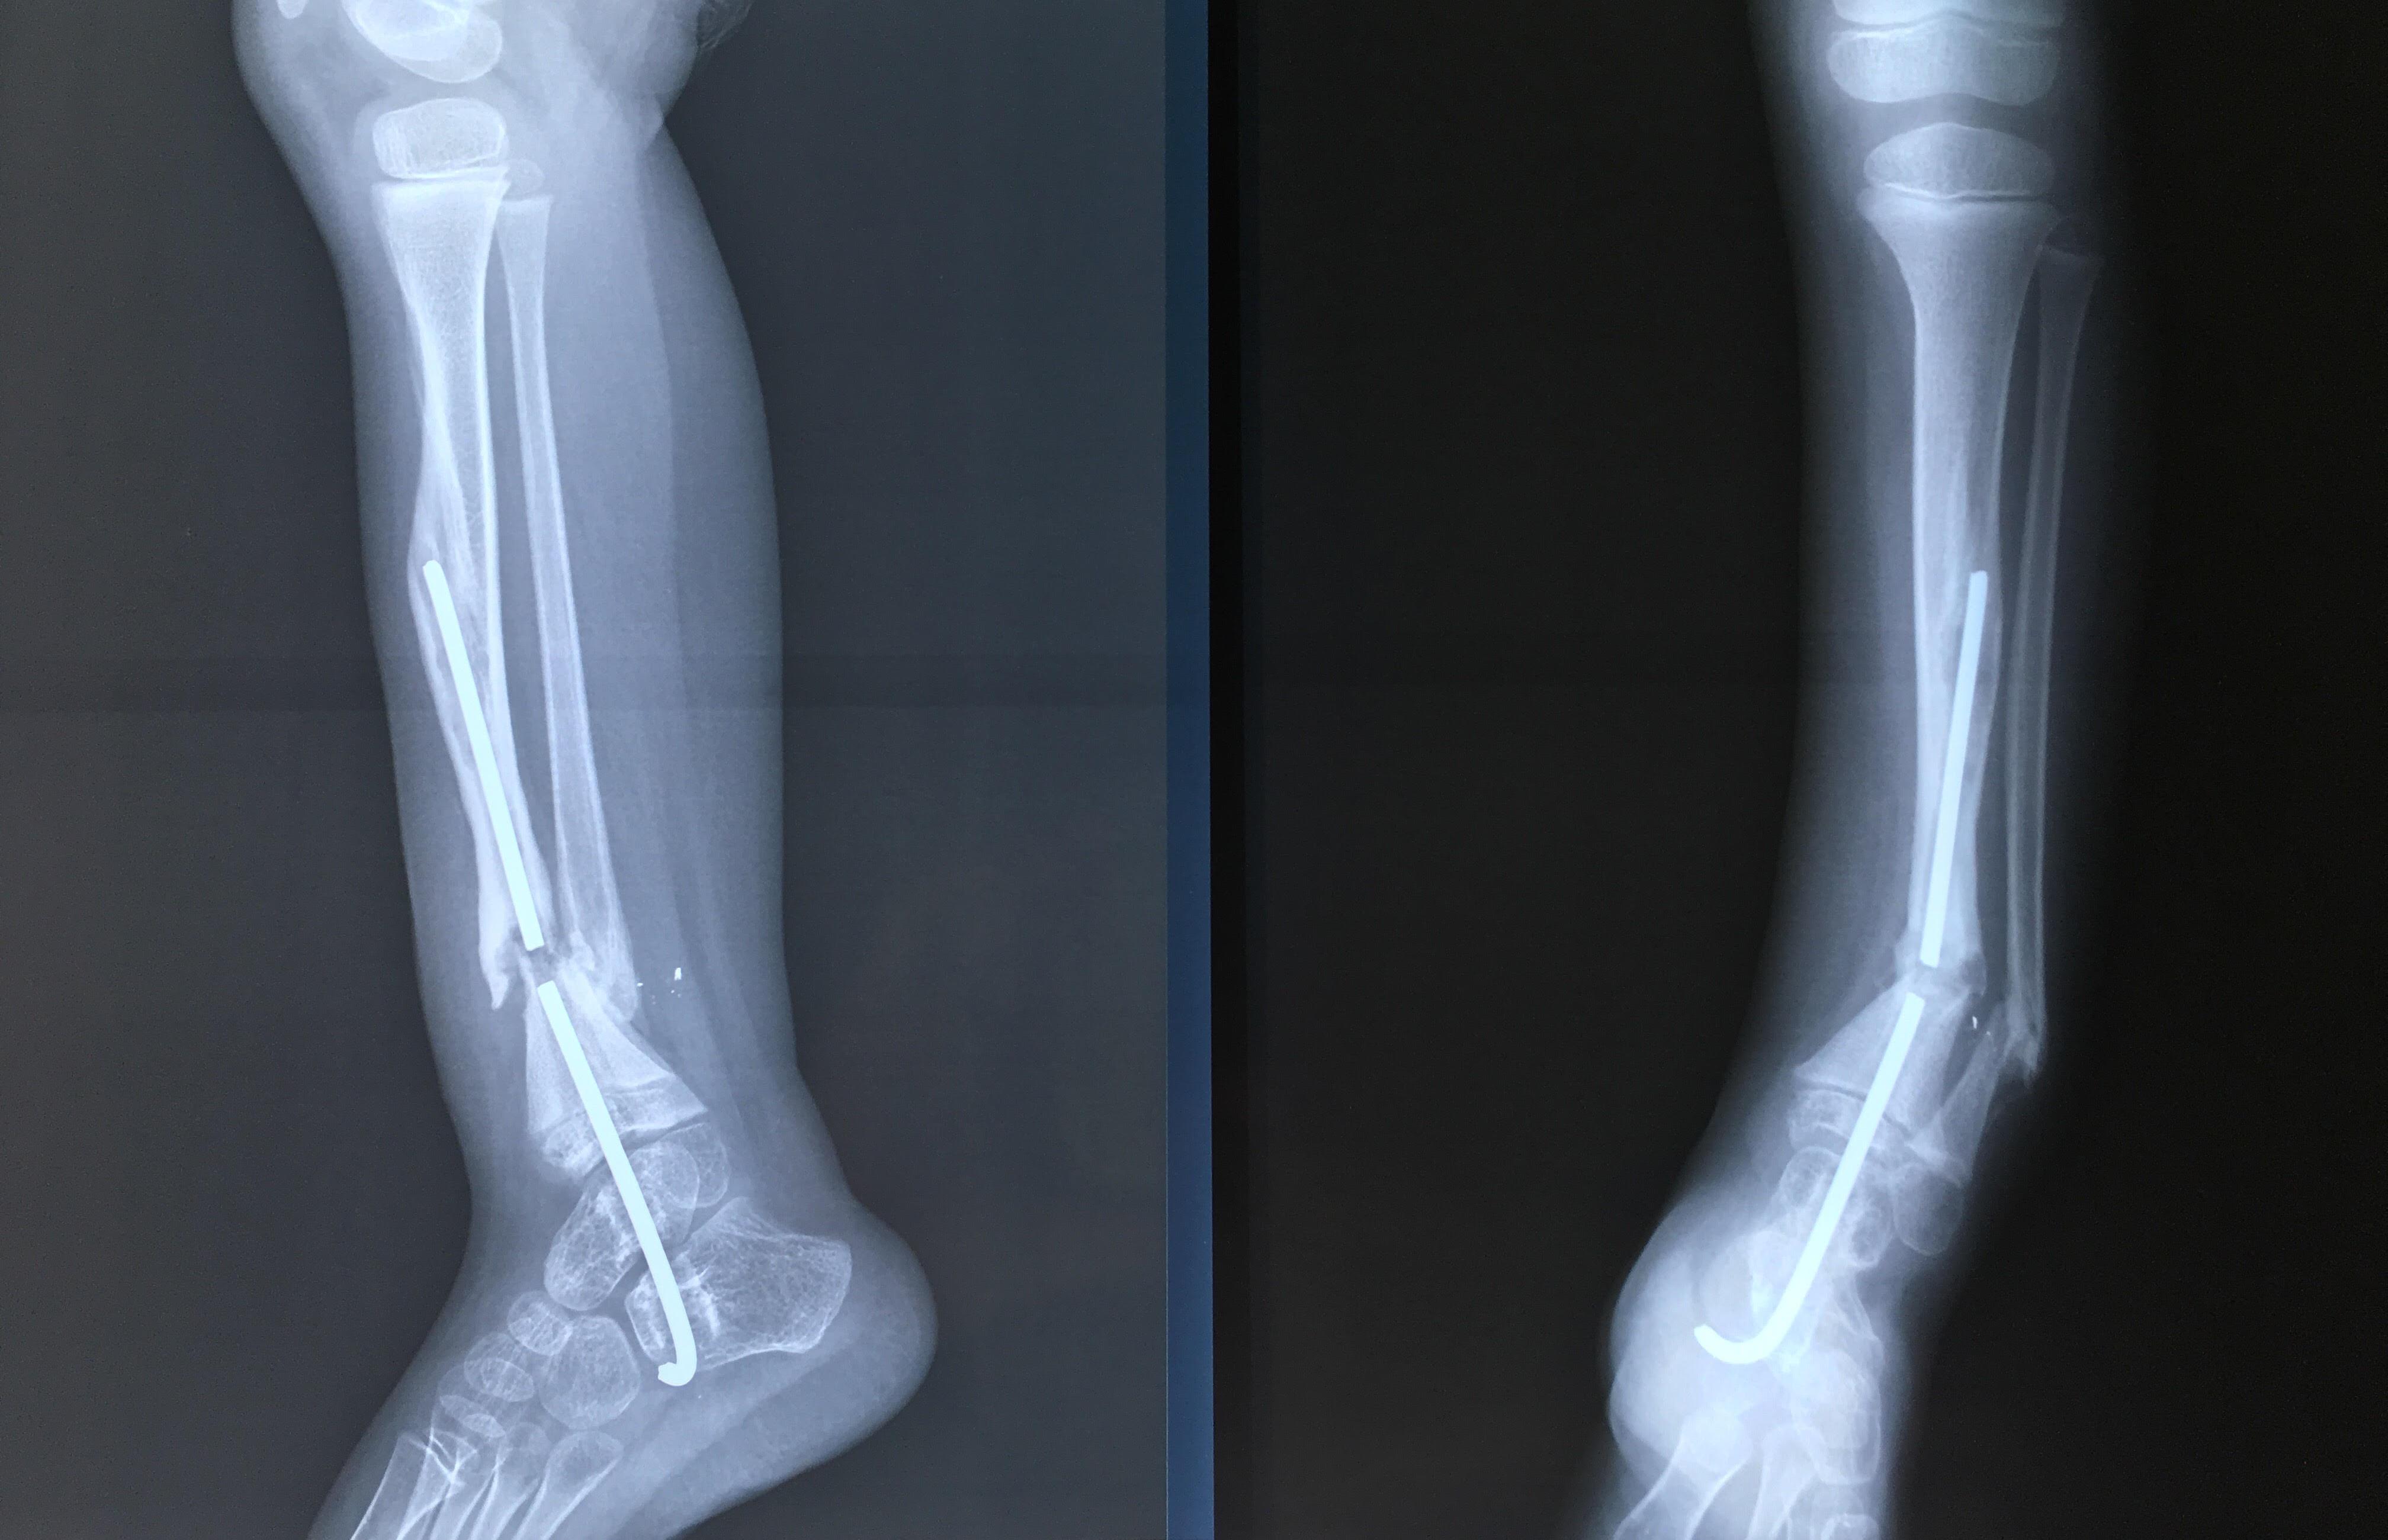

Phẫu thuật thành công ca bệnh hiếm gặp...khớp giả bẩm sinh xương chày

26/06/2019 17:00

Đã xem: 3183

Bệnh viện Chấn thương- Chỉnh hình Nghệ An, vừa phẫu thuật thành công cho bệnh nhi khớp giả bẩm sinh xương chày